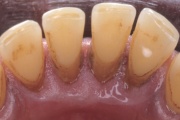

Krooniline parodontiit

Krooniline parodontiit on mikroobide poolt põhjustatud hammaste tugikudede põletik, mille tulemusena tekib progresseeruv alveolaarluu (nähtav röntgenograamil) ja periodontaalligamendi destruktsioon, igemetaskute moodustumine, igeme retsessioon või mõlemad kahjustused kombineeritult. Loe edasi »

- puudulik suuhügieen (5)

- igemepealne hambakivi (5)

- igemealune hambakivi (4)